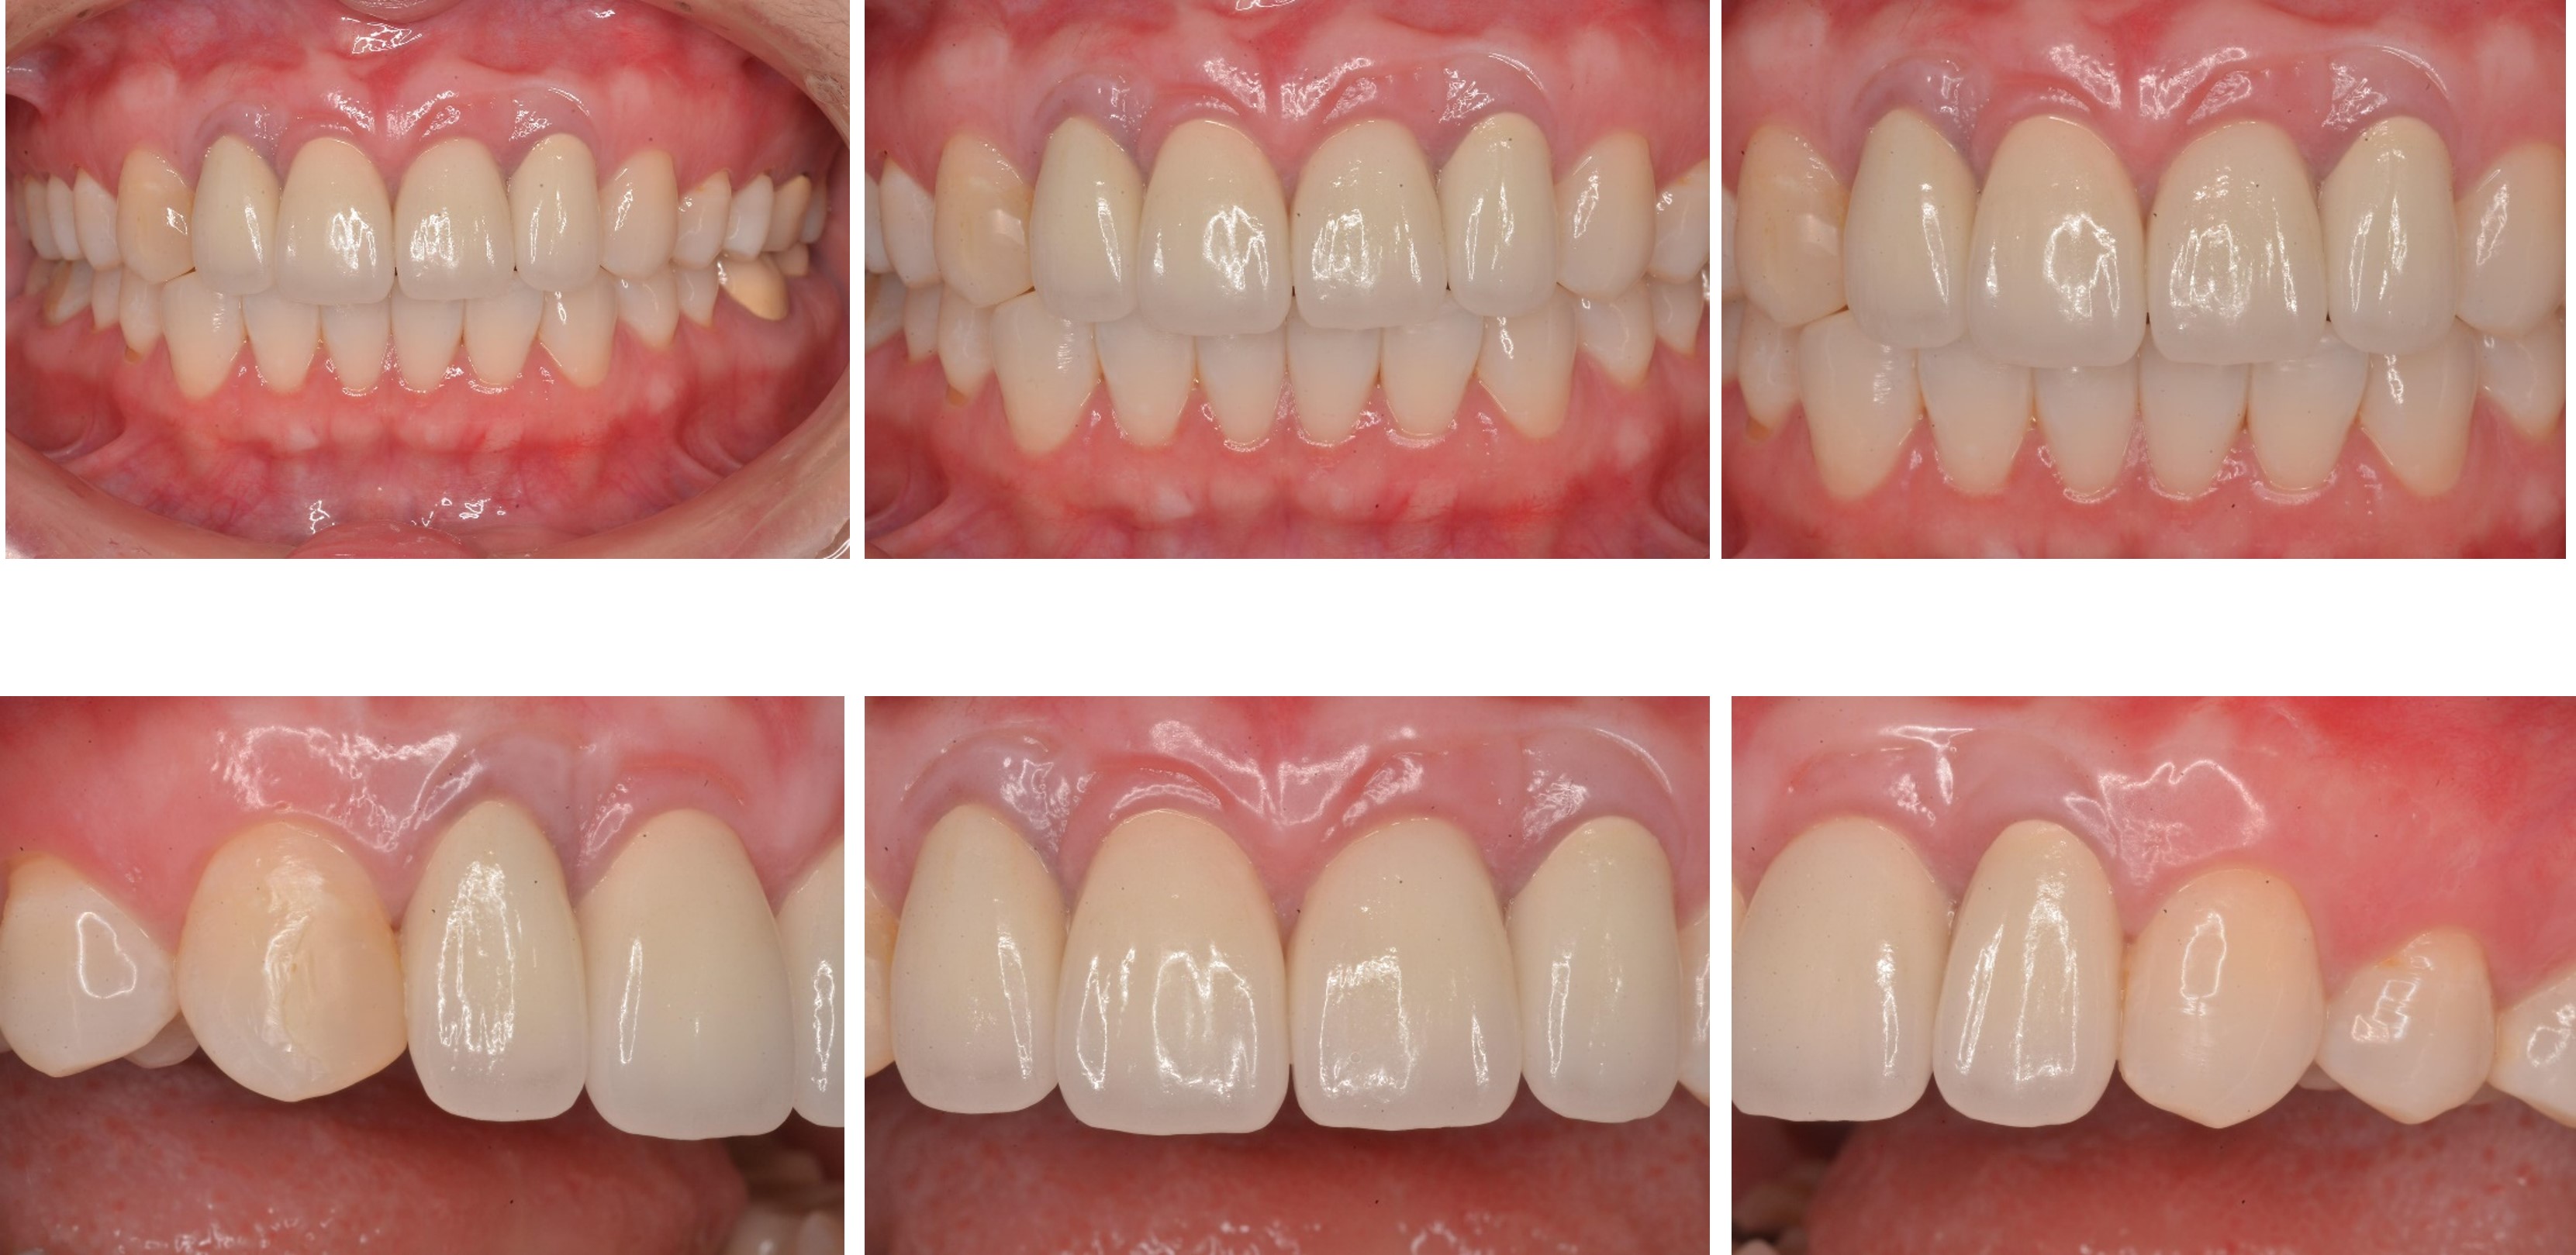

美白前,牙齒預比色-B3

美白前,微笑分析

居家美白1個月後再評估-A1

前牙全瓷冠

前牙美觀與功能兼顧

微笑時,患者開心